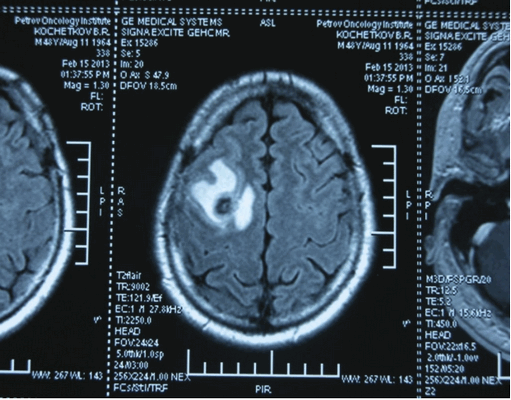

Головной мозг

Герминогенные новообразования в данной области - это примерно 2-4% от всех внутричерепных (интракраниальных). Патология в 75% случаев диагностируется у мальчиков, за исключением турецкого седла, где новообразования в основном локализуются у девочек.

Герминомы формируют инфильтрирующие опухоли больших размеров, часто являющиеся источниками субарахноидальных (между мягкой и паутинной оболочками мозга) и вентрикулярных (желудочковых) метастаз.

Рисунок 7. - Герминома головного мозга.

- КТ (расшифровка: компьютерная томография), МРТ (расшифровка: магнитно-резонансная томография), ПЭТ-КТ (расшифровка: позитронно-эмиссионная томография, совмещенная с КТ). Эти обследования необходимы, чтобы рассмотреть структуры организма послойно и визуализировать опухоль. Они показывают, как сильно распространен патологический опухолевый процесс на находящиеся рядом ткани и органы, есть ли поражение костей. КТ - это самый чувствительный метод для обнаружения метастазов в легких. Проведение МРТ и КТ головного мозга необходимо, чтобы обнаружить и визуализировать герминогенные новообразования эпифиза.

Рисунок 9. - метастаз в головной мозг при герминогенной опухоли.

Лечение

Лучевая терапия показана чаще при локализации процесса в головном мозге. Она позволяет точно, локально воздействовать на опухоли.

Забрюшинные герминогенные опухоли длительное время протекают бессимптомно. Могут проявляться диспепсией, болями в животе, дизурией, одышкой, отеками и варикозным расширением вен нижних конечностей. При злокачественных поражениях на поздних стадиях выявляются симптомы раковой интоксикации. Герминогенные опухоли крестцово-копчиковой зоны обычно диагностируются у детей раннего возраста и протекают доброкачественно. При крупных неоплазиях наблюдаются боли и слабость в нижних конечностях, нарушения дефекации и дизурия. Возможны кровотечения и некроз. Внутричерепные герминогенные опухоли чаще локализуются в зоне эпифиза, иногда - в области гипоталамуса либо гипофиза. Проявляются головной болью, тошнотой, рвотой и расстройствами движений глазных яблок.

Герминогенные опухоли центральной нервной системы (головного мозга) имеют следующие клинические проявления: головная боль, расстройство движений глазных яблок, тошнота, рвота и развитие судорог.

Также выполняют МРТ головного мозга, чтобы выявить наличие метастазов в нем.

Лучевая терапия назначается чаще при поражении головного мозга. Ее применение обусловлено возможностью точного локального воздействия на опухолевые массы.